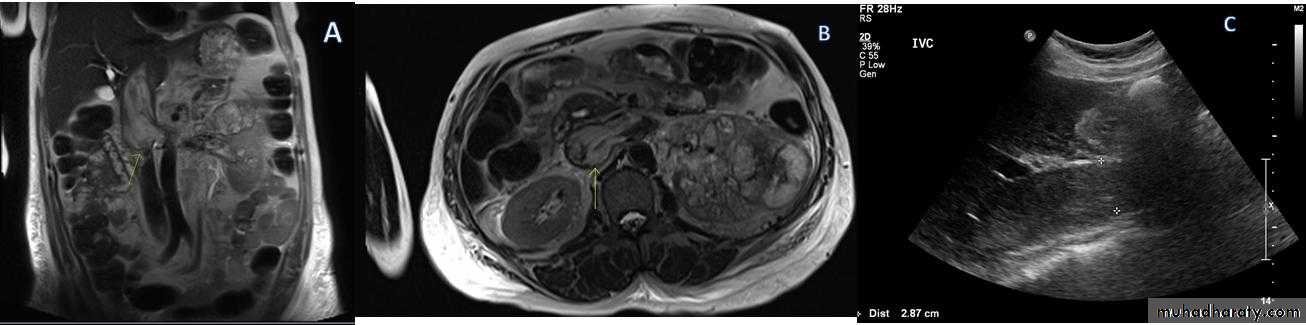

• IVC or renal vein extension of renal tumors.

Staging is best by CT except for vascular invasion where MRI will be superior.

Staging parameters include : local direct spread, retroperitoneal L.Ns enlargement, liver adrenal or pancreatic metastasis and renal vein or IVC involvement.